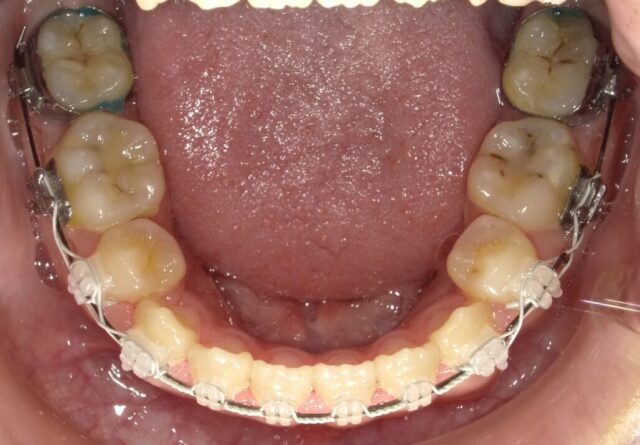

≪下顎咬合面観≫

2023年5月

2023年6月

2023年7月

2023年8月

2023年9月

2023年10月

2023年11月

2023年12月

2024年1月

2024年2月

2024年3月

2024年4月

2024年5月

2024年6月

2024年7月

2024年8月

2024年9月

2024年10月

2024年12月

2025年1月